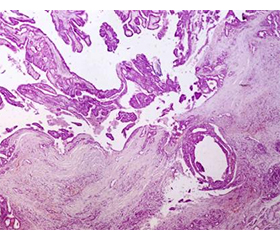

Papillary thyroid carcinoma (PTC) is the most common form of thyroid cancer in children, although its presentation in this age group remains rare. PTC, despite having a good prognosis, can present more aggressively in children than in adults. Diagnosis typically begins with physical examination and ultrasound, followed by fine-needle aspiration biopsy (FNAB) for cytological assessment using the Bethesda system. Standard treatment for PTC is surgery — lobectomy or total thyroidectomy depending on disease spread, cytological findings, and patient profile. This paper presents the clinical case of a 9-year-old female patient with a suspicious thyroid nodule, successfully treated through thyroid lobectomy. Ultrasound revealed a solid, hypoechoic nodule with microcalcifications in the right thyroid lobe. FNAB returned a Bethesda V classification, raising suspicion for papillary carcinoma. After a multidisciplinary evaluation by the medical team (endocrinologist, surgeon, cytopathologist, radiologist, pediatric oncologist), a right thyroid lobectomy was decided upon for both diagnostic and therapeutic purposes. During surgery, a well-confined nodule was identified with no apparent invasion into surrounding tissues. Histopathological analysis confirmed papillary thyroid carcinoma, follicular variant, no vascular or extrathyroidal invasion, no metastases in the examined lymph nodes. These findings suggested a localized disease form with an excellent prognosis. Following the intervention, the patient recovered without complications: vital parameters remained stable, with no signs of bleeding or local infection; follow-up ultrasound at 6 weeks showed no residual formations, and normal structure of the left lobe and surrounding tissues. There was no need for total thyroidectomy or radioactive iodine therapy, in accordance with current protocols for localized cases. The importance of early diagnosis, appropriate surgical treatment, and careful clinical follow-up is discussed, as well as the role of a multidisciplinary team in managing pediatric endocrine oncology cases.